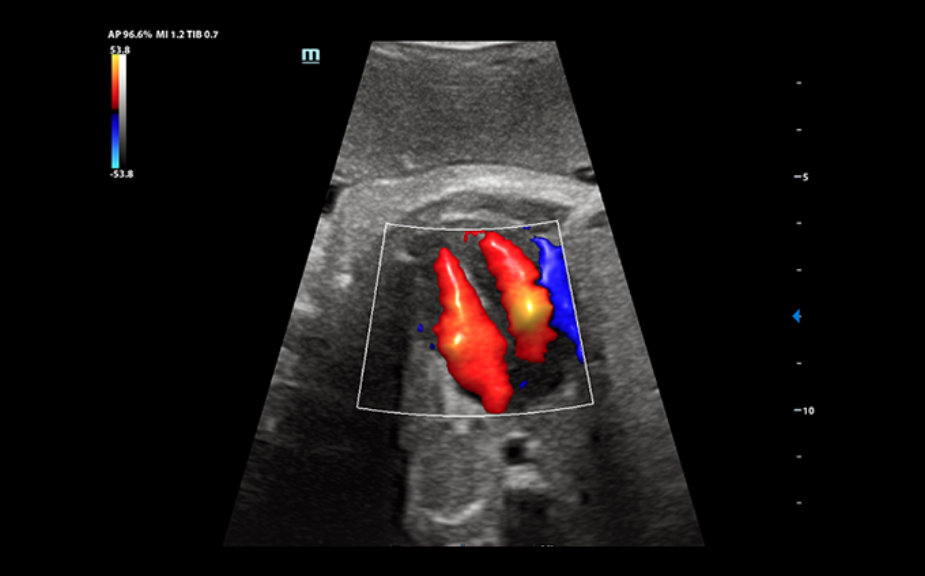

ImĂĄgenes clĂnicas